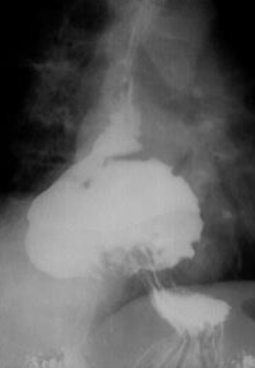

Ulcer gastric